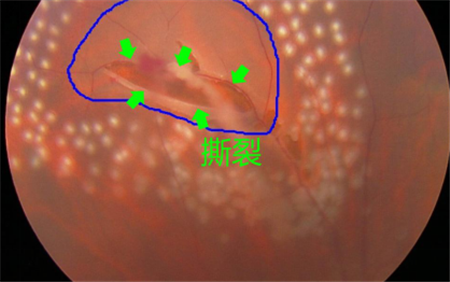

視網(wǎng)膜退化以及撕裂、后玻璃體脫落、葡萄膜炎、糖尿病或者黃斑變性引起的眼底出血等,可導(dǎo)致飛蚊癥產(chǎn)生,這種情況就屬于惡性飛蚊。雖然飛蚊本身并不會(huì)導(dǎo)致眼睛失明,但這些原發(fā)疾病若不及時(shí)治療,失明的風(fēng)險(xiǎn)卻是非常大的。

所以在出現(xiàn)飛蚊癥時(shí),建議上醫(yī)院做個(gè)檢查,看看屬于哪一種飛蚊。尤其是突然出現(xiàn)大量飛蚊、閃光,并伴隨視力下降或者視野缺損的情況,更需要及時(shí)就醫(yī)。在上海眼科醫(yī)院排名治療惡性飛蚊需要結(jié)合患者的原發(fā)疾病進(jìn)行治療,比如由視網(wǎng)膜裂孔導(dǎo)致的飛蚊癥,需要通過(guò)激光治療將裂孔封閉,從而避免視網(wǎng)膜進(jìn)一步脫落。